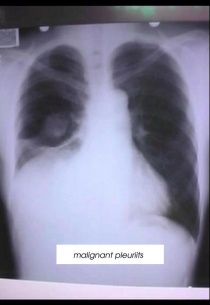

При по-тежки случаи на заболяването се наблюдава и плеврален излив. Течността се премахва със специална тръбичка, поставена на гърдите.